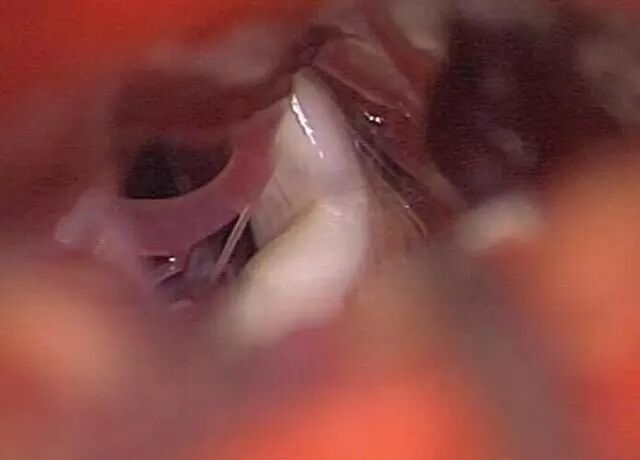

图为典型的原发性三叉神经痛图片,可见血管与三叉神经交叉处有明显压痕(来源:Demetriades AK, Gullan RW.Impressive Vascular Compression of the Trigeminal Nerve[J].Mayo Clin Proc,2011,86(12):e53.)